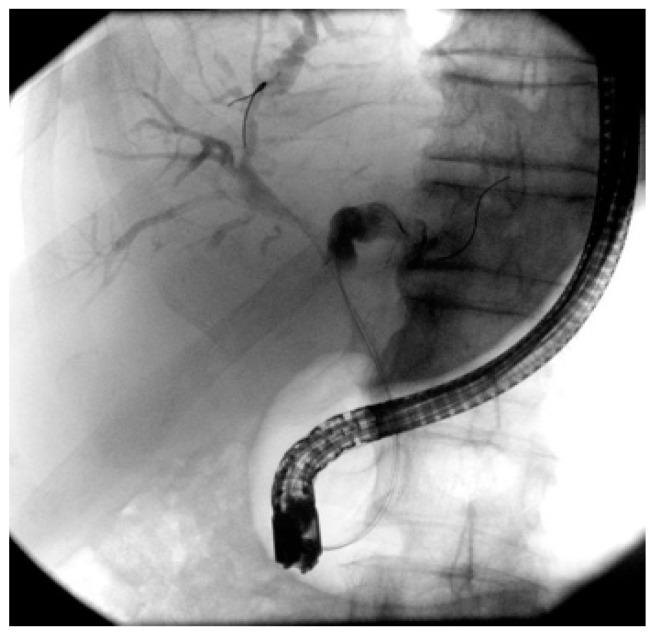

This review aims to focus on what we know about the management of biliary strictures of unknown etiology, especially exploring our diagnostic armamentarium in the setting of indeterminate biliary strictures. Presently, this is a current issue that has a relevant impact both on patient prognosis, often delaying diagnosis, and on overall costs associated with repeating diagnostic procedures, sometimes performed with very expensive devices. We also focus on current biliary drainage approaches, providing an overview of therapeutic options, endoscopic or not.

本综述旨在聚焦于我们对病因不明的胆管狭窄的管理所知,尤其探索在不确定胆管狭窄情况下的诊断手段。目前,这是一个当前的问题,对患者预后(常常延误诊断)以及与重复诊断程序相关的总体成本都有相关影响,有时这些诊断程序使用非常昂贵的设备进行。我们还关注当前的胆管引流方法,概述治疗选择,无论是否为内镜治疗。